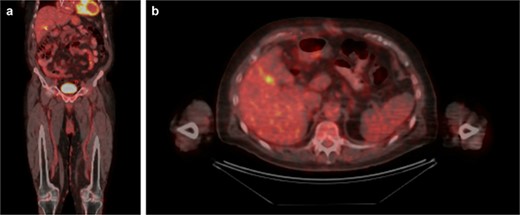

An 81-year-old male presented with the chief complaint of sharp right upper quadrant abdominal pain and nausea ongoing for 12 hours. The patient reported a similar, self-limited, episode 3 months previously. On presentation, leukocytosis 13 × 109/l, aspartate aminotransferase 83 U/l, alanine aminotransferase 49 U/l, lipase 78 U/l (normal 15–65), and total bilirubin 0.7 mg/dl. Abdomen and pelvis computed tomography (CT) demonstrated cholelithiasis in the gallbladder neck, soft tissue attenuation in the fundus of the gallbladder, mild extrahepatic biliary dilation and a common bile duct dilated to 10 mm (Fig. 1). Two well-circumscribed rounded filling defects within the gallbladder lumen, measuring 4.7 × 2.8 × 2.5 cm and 3.4 × 1.4 × 2.2 cm without distal shadowing, were visualized on right upper quadrant ultrasound (Fig. 2). CA 19-9 was negative (6.0 U/l). Magnetic resonance (MR) imaging was unable to be safely performed due to a metal prosthesis.

CT abdomen/pelvis without contrast. (A) Coronal and (B) axial slices depicting cholelithiasis, soft tissue within the gallbladder lumen and extrahepatic biliary ductal dilation